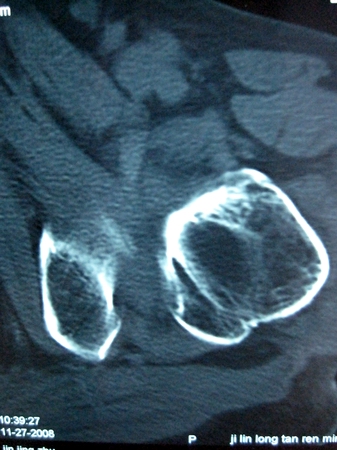

以下是引用lkc8963在2008-12-19 21:19:00的发言:[br]左?右?患侧大转子上移,股骨颈骨质浓杂,髋周见多发条片状骨化影,以小转子为著,多为陈旧性股骨颈骨折后改变并骨化性肌炎.请咨询既往史!